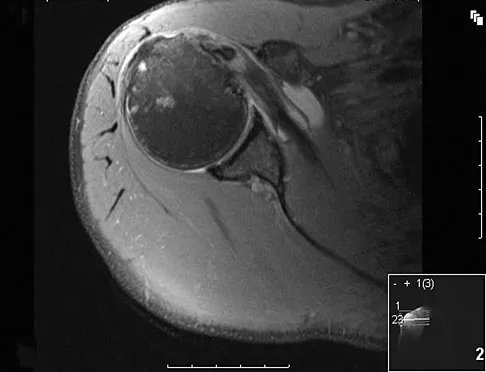

A newborn girl with an isolated unilateral dislocatable hip is placed in a Pavlik harness with the hips flexed 100 degrees and at resting abduction. Figure 23 shows an ultrasound obtained 2 weeks later. What is the next step in management?

The infant has a well-positioned hip in the Pavlik harness and treatment should be continued in the current position. The success rate is over 90% with the use of this device for a dislocatable hip. Ultrasound is a useful tool to confirm appropriate positioning of the cartilaginous femoral head during treatment. If the femoral head is not reduced after 2 to 3 weeks in the harness, this mode of treatment should be abandoned. Forceful extreme abduction can cause osteonecrosis of the femoral epiphysis and should be avoided. Closed reduction, arthrography, and spica casting are indicated if the hip cannot be maintained in a reduced position with the harness. Lehmann HP, Hinton R, Morello P, et al: Developmental dysplasia of the hip practice guideline: Technical report. Committee on Quality Improvement, and Subcommittee on Developmental Dysplasia of the Hip. Pediatrics 2000;105:E57.